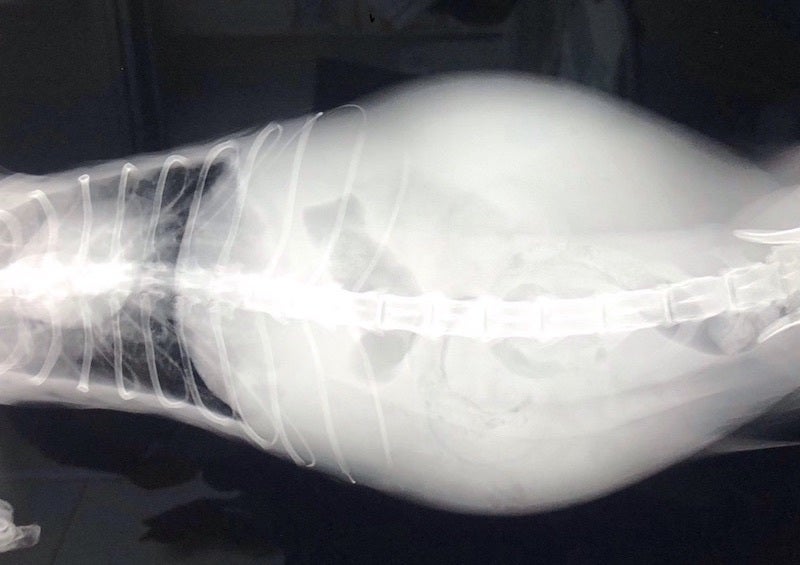

FIPという診断を受けた時に、あらゆる手段を使いこの病気について調べました。動物病院の先生やネットで調べた結果、外猫・野良猫のほとんどが持っているコロナウイルスが突然体内で変異し、FIPウイルスになるということが分かりました。FIPウイルスは一度発症してしまうと元に戻ることはありません。原因はストレスのことが多いと言われており、ずら丸にストレスを与えてしまっていたと日々嘆くばかりです。現在の症状としては腹水・胸水の貯留、食欲減退、便秘、黄疸、脱水症状です。動物病院への通院で脱水症状については収まりを見せていますが、その他は改善の兆しが見えてきません。

腹部レントゲン画像

ずら丸の腹水が溜まっているのを見た際、リンパ癌や心臓の病気など様々な病気を疑いました。しかし考えていたよりも状況は重く、不治の病と言われるFIPでした。世界中にFIPで苦しんでいる猫、オーナー様はいらっしゃいます。新薬での寛解を実証出来れば、今後のオーナー様のFIP治療の選択肢が広がるのではないかと考えています。